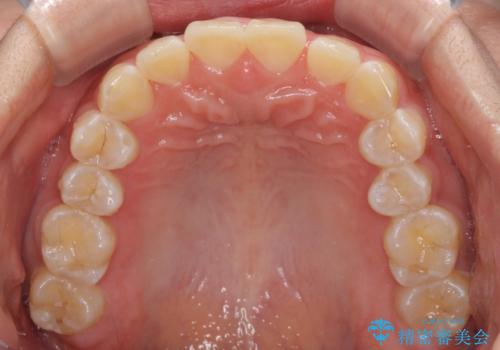

前歯の隙間と上下正中のズレを解消

- 上下前歯隙間と正中のズレを改善したいとのことで来院された患者様です。

自己管理を減らしたいとのことで、ワイヤー装置による矯正治療を行うこととしました。